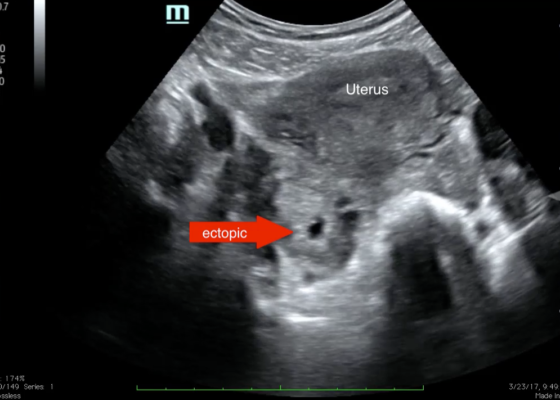

Point-of-care Ultrasound for the Diagnosis of Ectopic Pregnancy

DOI: https://doi.org/10.21980/J8VK7VThe transabdominal pelvic ultrasound shows an empty uterus (annotated) with free fluid and a right sided extrauterine gestational sac representing an ectopic pregnancy (red arrow).